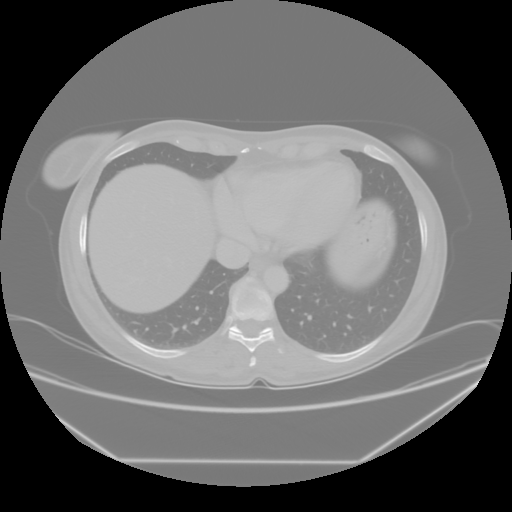

Reconstructed NATIVE CT scan (cycle consistency)

No window - Raw intensity values

Lung window (WL -600, WW 1500 β†’ Low βˆ’1350, High +150)

Mediastinum window (WL 40, WW 400 β†’ Low βˆ’160, High +240)